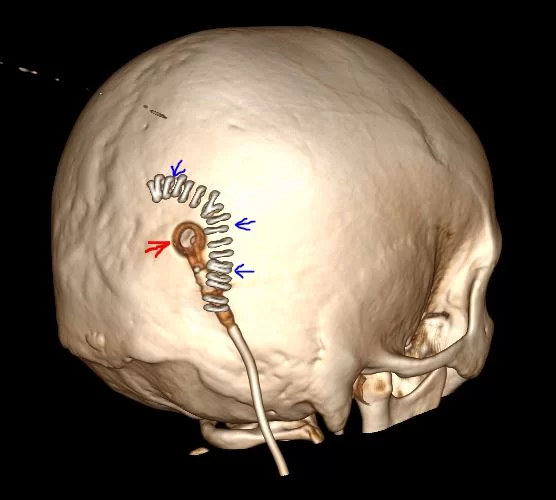

Η θεραπεία του υδροκεφάλου φυσιολογικής πίεσης είναι η τοποθέτηση κοιλιοπεριτοναϊκής παροχέτευσης (αναφερόμενη συχνά ως τοποθέτηση βαλβίδας). Αυτό που γίνεται είναι να τοποθετείται ένα πολύ λεπτό και μαλακό σωληνάκι απο σιλικόνη, το οποίο παροχετέυει το εγκεφαλονωτιαίο υγρό (ΕΝΥ) από τον εγκέφαλο στην περιτοναϊκή χώρα, δηλαδή στην κοιλιά του ασθενούς, όπου και απορροφάται.

(Προσωπικό αρχείο νευροχειρουργού Π. Σταυρινού).

Ο υδροκέφαλος αντιμετωπίζεται συνήθως με την εισαγωγή μιας κοιλιοπεριτοναϊκής παροχέτευσης ή αλλιώς «βαλβίδας». Πρόκειται για την τοποθέτηση ενός πολύ λεπτού και μαλακού καθετήρα απο σιλικόνη, με την παρεμβολή μιας μικρής βαλβίδας , από τον εγκέφαλο στην περιτοναϊκή κοιλότητα, δηλαδή στην κοιλιά. Αυτό το σύστημα εκτρέπει την ροή του ΕΝΥ από τον εγκέφαλο σε άλλη περιοχή του σώματος όπου μπορεί να απορροφηθεί ως μέρος της κανονικής κυκλοφοριακής διαδικασίας. Η βαλβίδα τοποθετείται κατά μήκος του καθετήρα και έχει σαν στόχο να διατηρεί μονόδρομη ροή και να ρυθμίζει την ταχύτητα της ροής του ΕΝΥ.